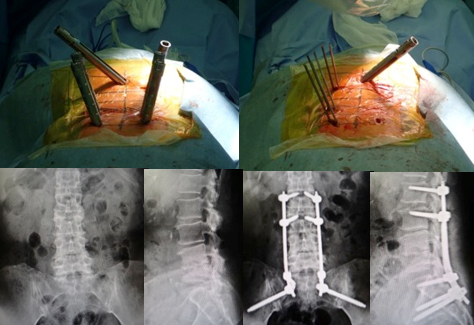

びまん性特発性骨増殖症、強直性脊椎炎に対するミスト手術

びまん性特発性骨増殖症や、強直性脊椎炎という、せぼねが連続して癒合(くっつく)してしまう病気があります。脊椎が癒合していない部分で狭窄を生じたり、軽微な外傷でも骨折を起こし、脊髄を圧迫して神経障害が出現することがあります。当院では、体にかかる負担の少ない経皮的椎弓根スクリューを用いた特殊な方法で、脊椎を安定化させるミスト手術を積極的に行っております。

があり、同部位で狭窄が生じ脊髄が圧迫されています。

に脊椎を安定化し、神経症状は著明に改善しました。